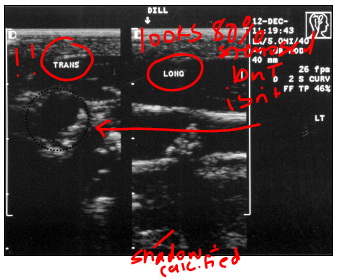

what are the benefits of getting an image in long?

anatomy - helps elongate

plaque characterization - shadows/mobile

Length of plaque

Doppler

what type of plaqe is this?

smooth CCA plaque

what type of plaque morphology is this?

irregular, complex